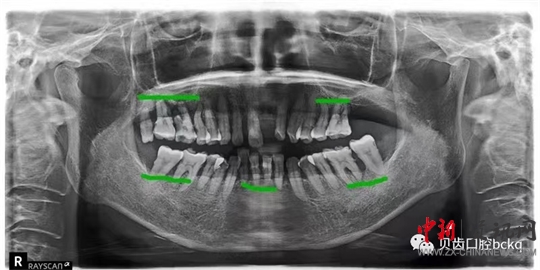

下面這兩張x光片是比較典型的牙周炎的影像資料。該患者的全口所有牙齒都出現了不同程度的松動;颊攥F在感覺無法用牙齒咀嚼。坦白地講,牙周炎發(fā)展到這種程度,很多時候醫(yī)生也束手無策了。為了保留更多的牙槽骨,醫(yī)生回不得不拔掉哪些嚴重松動的患牙。